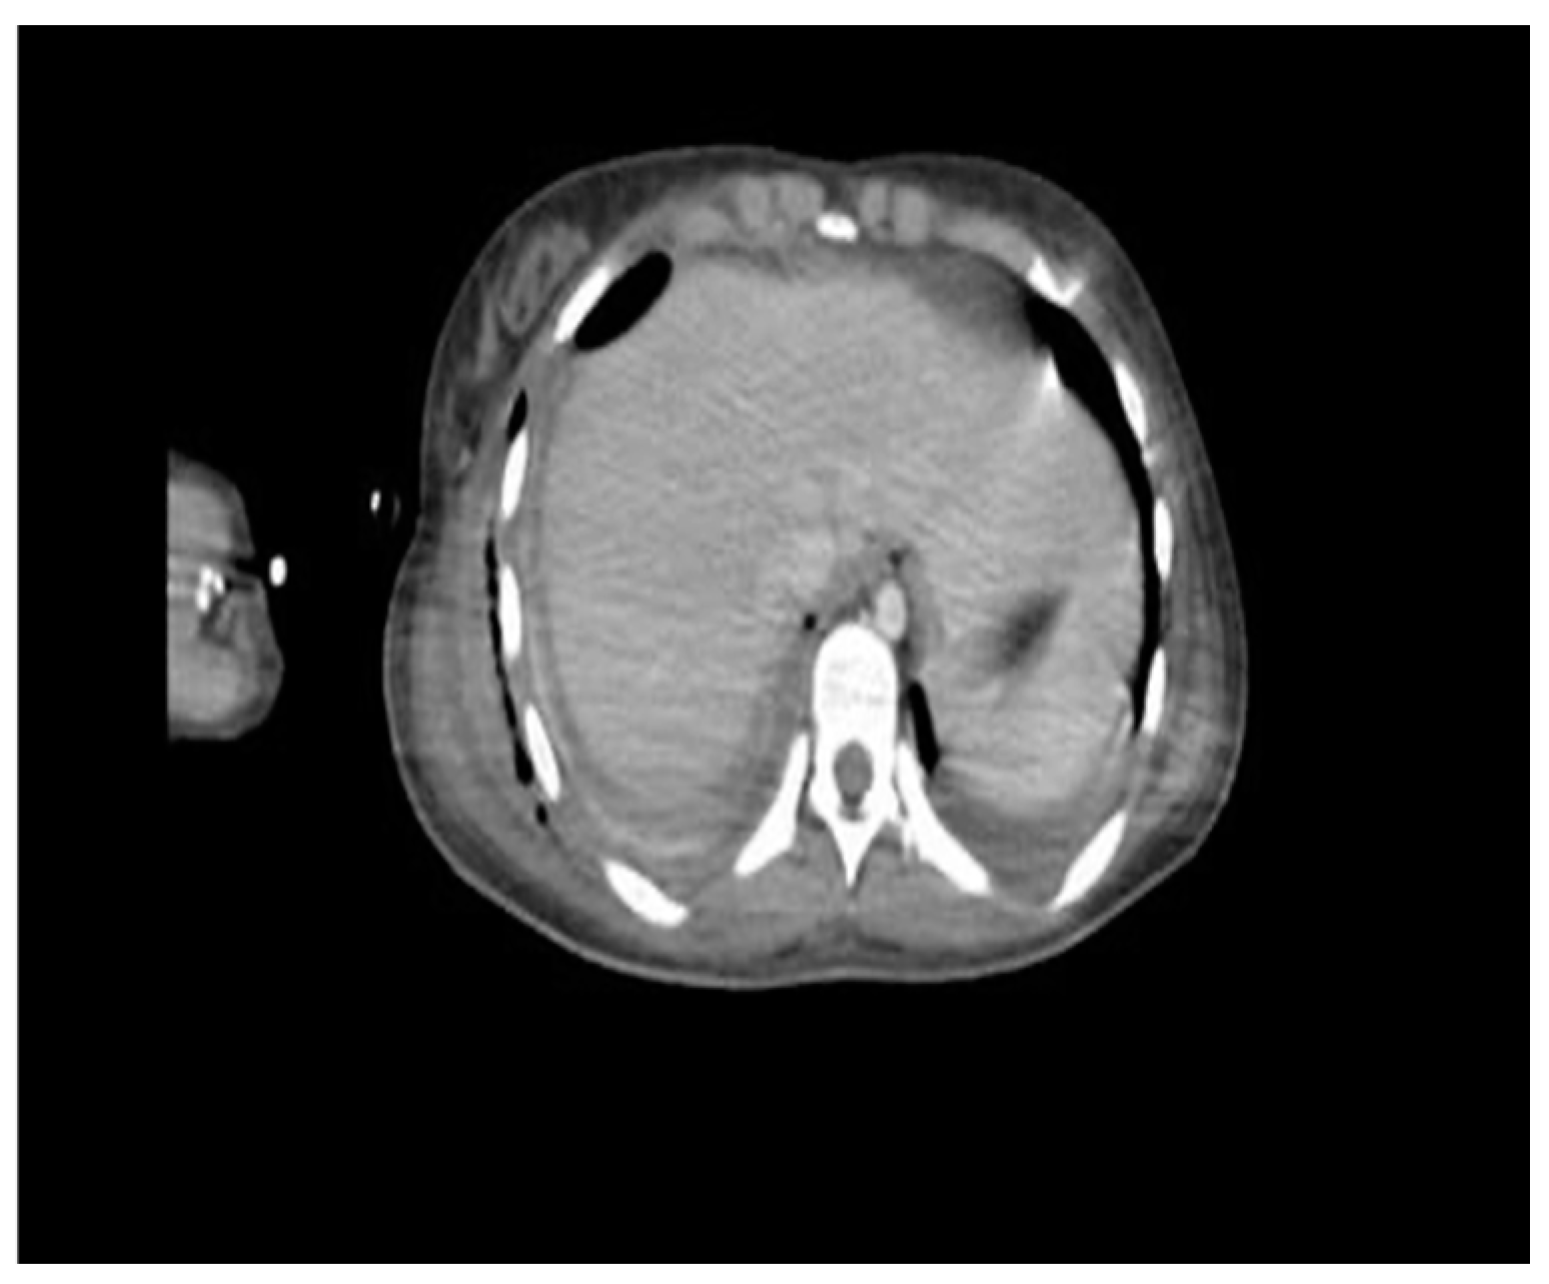

2. Case Presentation